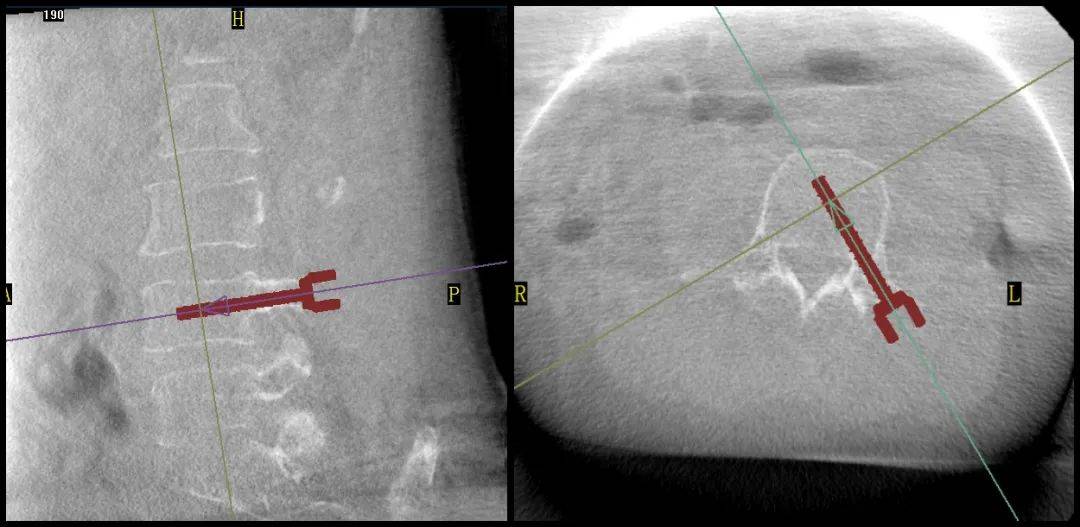

手術(shù)過(guò)程中,普愛(ài)醫(yī)療平板三維C形臂為患者拍攝了清晰的三維影像,醫(yī)生基于影像完成了兩個(gè)節(jié)段的穿刺路徑規(guī)劃。

普愛(ài)醫(yī)療品牌骨科手術(shù)機(jī)器人的機(jī)械臂憑借高精度導(dǎo)航能力,引導(dǎo)醫(yī)生一次性精準(zhǔn)穿刺,憑借超大內(nèi)傾角度單通道抵達(dá)椎體中央位置,達(dá)到雙通道的骨水泥彌散效果,成功完成兩節(jié)跨節(jié)段椎體的骨水泥注入。